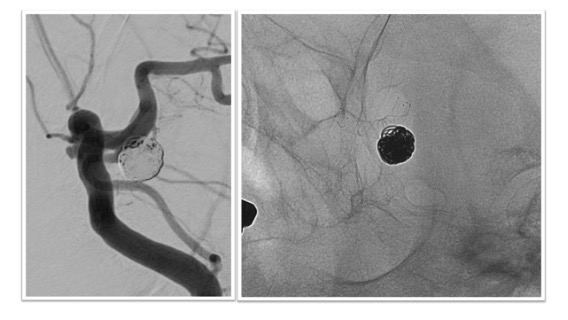

ステント併用コイル塞栓術治療実例(*患者様の許可を得て掲載しています)

内頸動脈後交通動脈分岐部(ICPC)動脈瘤

ICPCの動脈瘤へのステント併用コイル塞栓術後の脳血管撮影画像とレントゲンです。血管撮影画像から脳血管ステントを併用することで動脈瘤が塞栓され、動脈瘤から分枝している後交通動脈の血流は温存されている様子がわかります(図左 血管撮影)。内頸動脈で展開されたステントが壁となることで動脈瘤に充填された塞栓用コイルが内頸動脈や後交通動脈側にはみ出さぬようになっています(図右 レントゲン)。